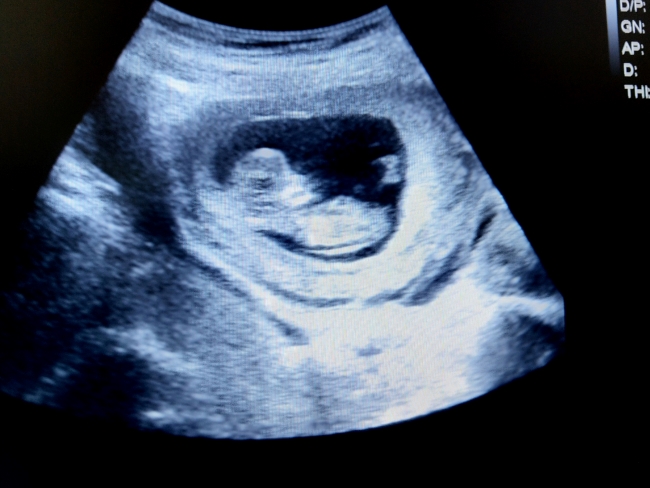

Ketika Bunda melakukan pemeriksaan USG, Bunda akan melihat bentuk janin mulai terlihat seperti manusia lho. Ini karena ekor janin sudah hilang dan fitur wajahnya, seperti mata, mulut, dan hidungnya sudah makin terlihat jelas daripada minggu-minggu sebelumnya. Begitu juga dengan bagian tubuh lain, seperti telinga, tangan, kaki, dan jari-jarinya.

Nah, jawaban dari pertanyaan janin 2 bulan apakah sudah bernyawa atau belum adalah sudah ya Bun. Karena di usia ini jantung janin sudah terbentuk dan berkembang dengan pesat. Bahkan, jantung janin sudah mulai berdetak dan biasanya dapat terdeteksi melalui USG sejak usia kehamilan 6 minggu.